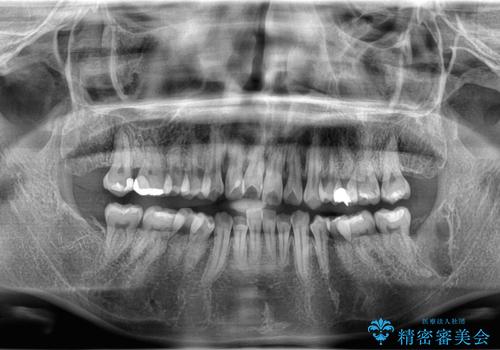

3. 【埋伏智歯と埋伏智歯の過剰歯の抜歯】埋まっている親知らず2本の抜歯の治療後

3.